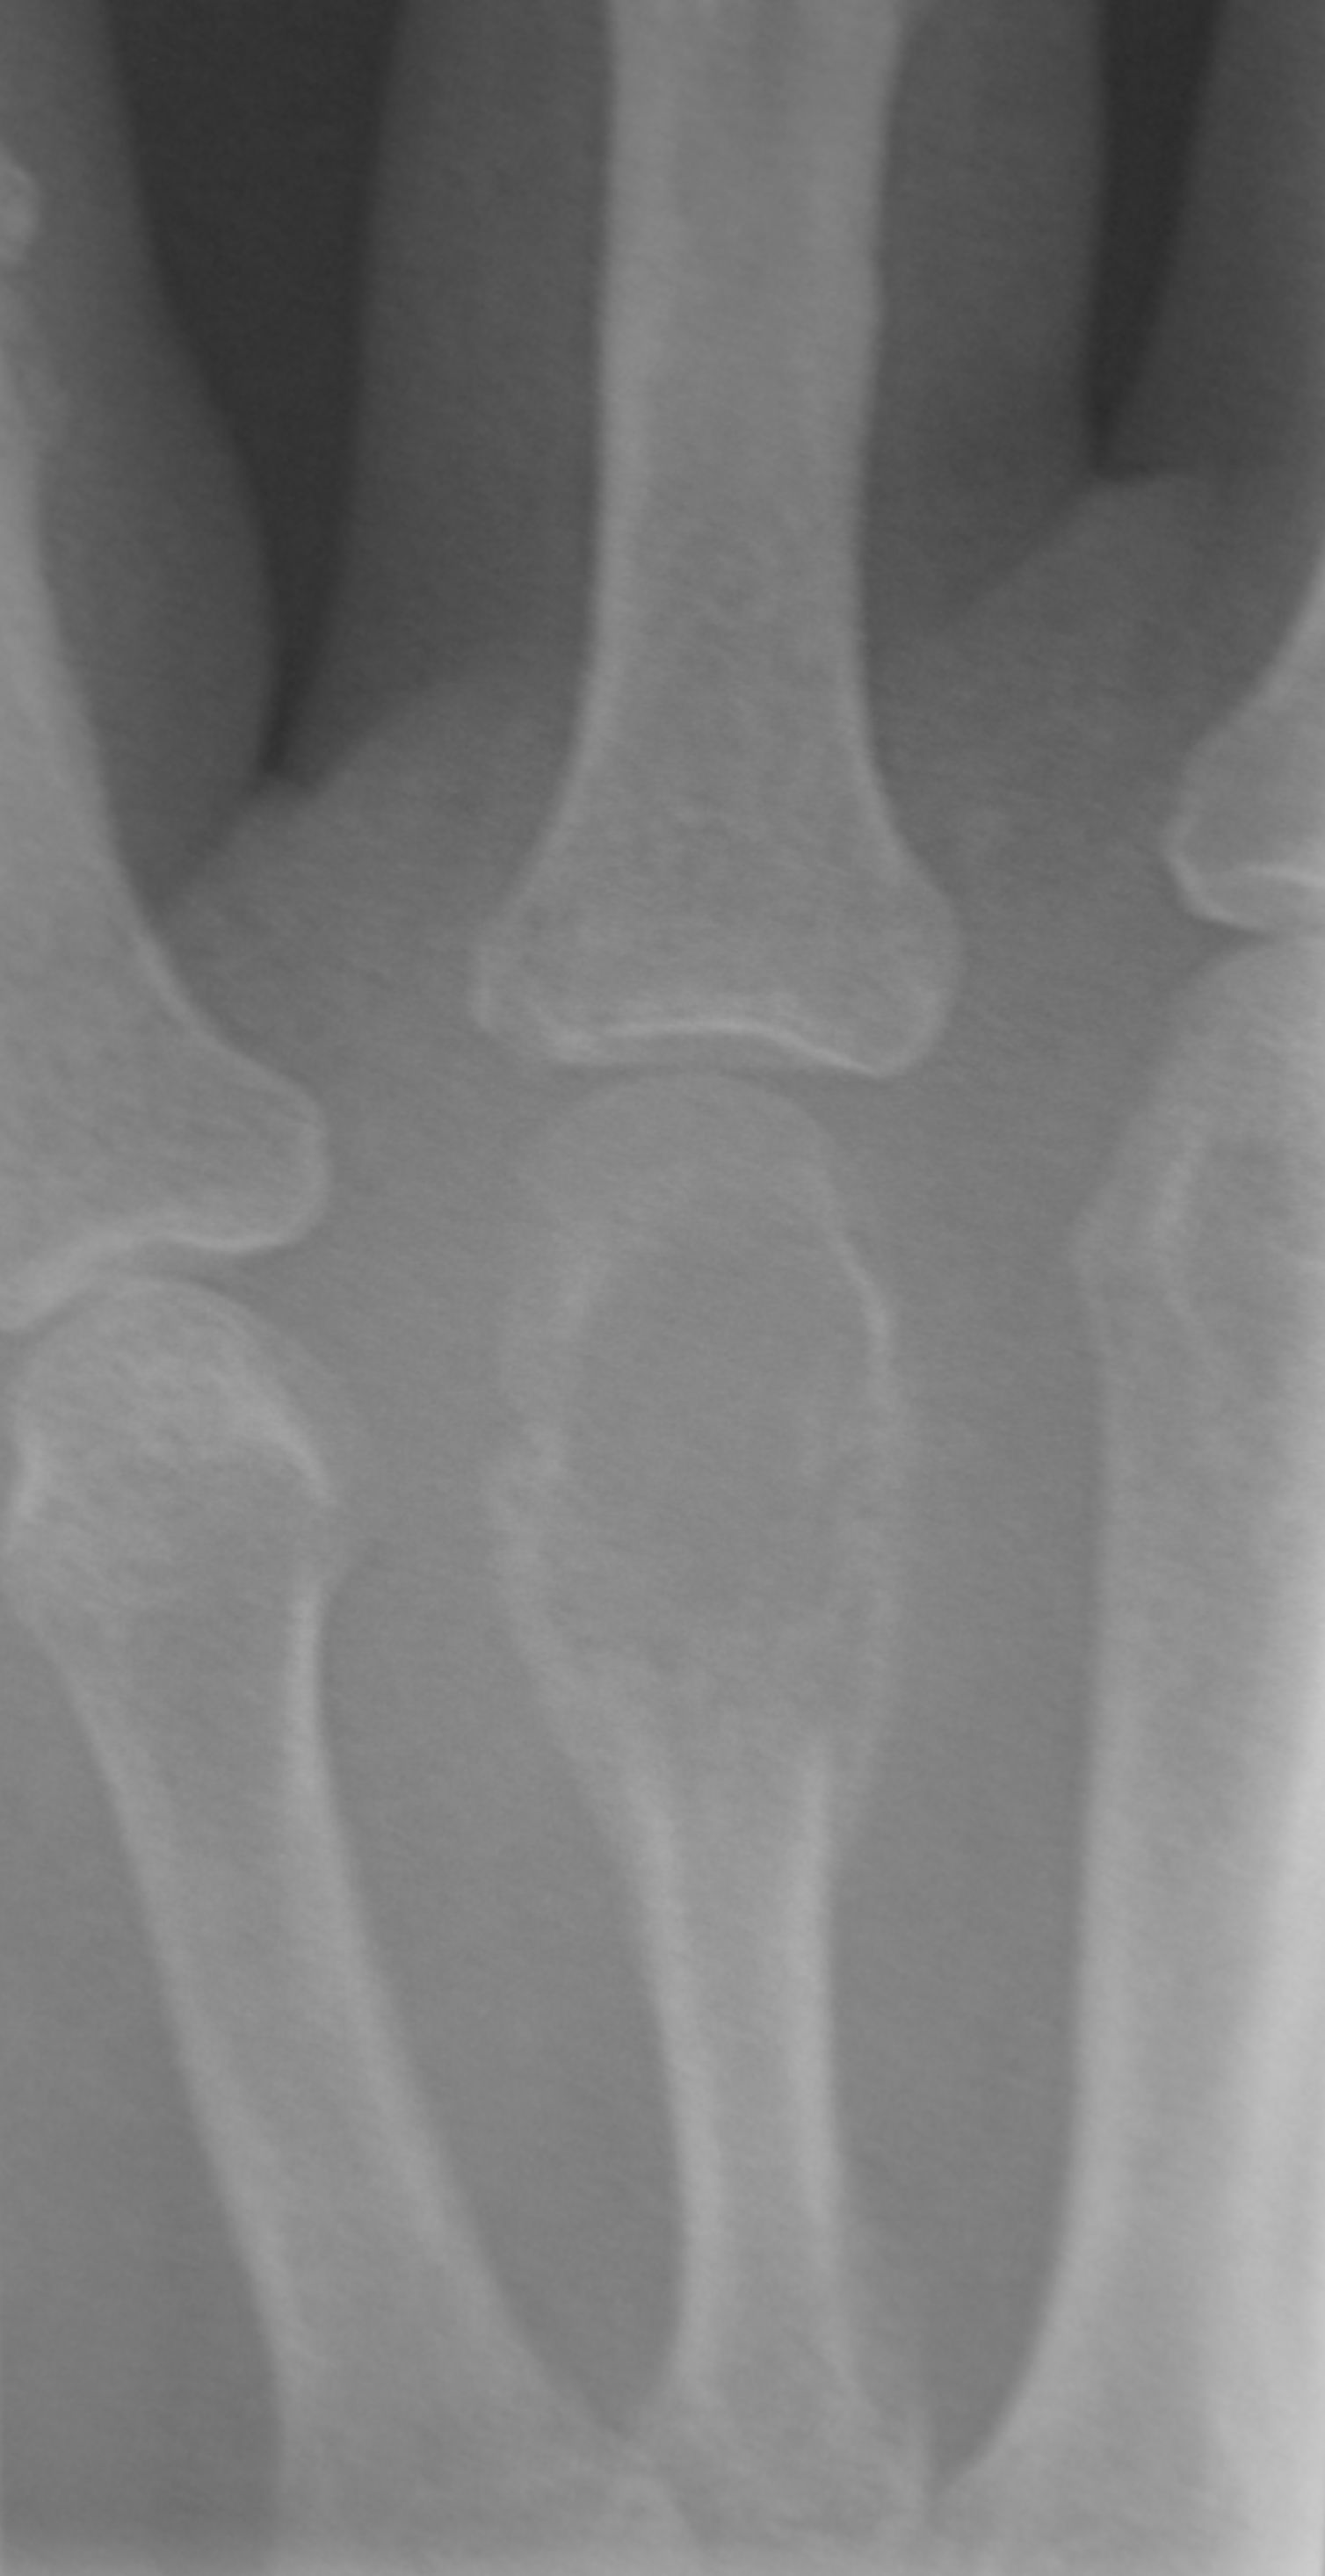

- 듀피트렌 구축 : 원인 불명의 IP 관절, MP 관절에서의 굴곡 구축을 일으키는 질환으로, 남성에게 많다.

- 헤버딘 결절

- 부샤르 결절

- 변형성 모지 수근 중수 관절증